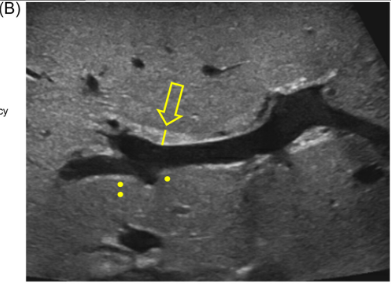

Background: Hepatic hemangiomas are one of the visceral hemangiomas that can be seen and are categorized as infantile or congenital.1, 2 Infantile hepatic hemangiomas (IHH) develop in the first weeks-to-months of life, reach peak size typically by 3 months and often spontaneously involute without medical management within 1–2 years.3 Congenital hepatic hemangiomas (CHH) are present at birth and may rapidly involute, partially involute, or remain static for life.

Guidelines for screening with imaging and laboratory evaluation have been previously published and highlight differences between IHH and CHH.2 (Reference: Iacobas I, Phung TL, Adams DM, et al. Guidance document for hepatic hemangioma (infantile and congenital) evaluation and monitoring. J Pediatr. 2018; 203: 294-300 e2).” Screening with blood counts, fibrinogen, liver function tests, alpha-fetoprotein (AFP), thyroid function tests (TFTs), should be performed at diagnosis for both types of hemangiomas with frequency of repeat testing depending on whether IHH or CHH is diagnosed.2 Echocardiogram at diagnosis should be considered in both if patients have symptoms of cardiac failure. Serial monitoring with liver ultrasounds for at least 1 year or until stable size and vascularity twice in a row is recommended for CHH whereas continued monitoring with ultrasound until complete involution is recommended for IHH.2“